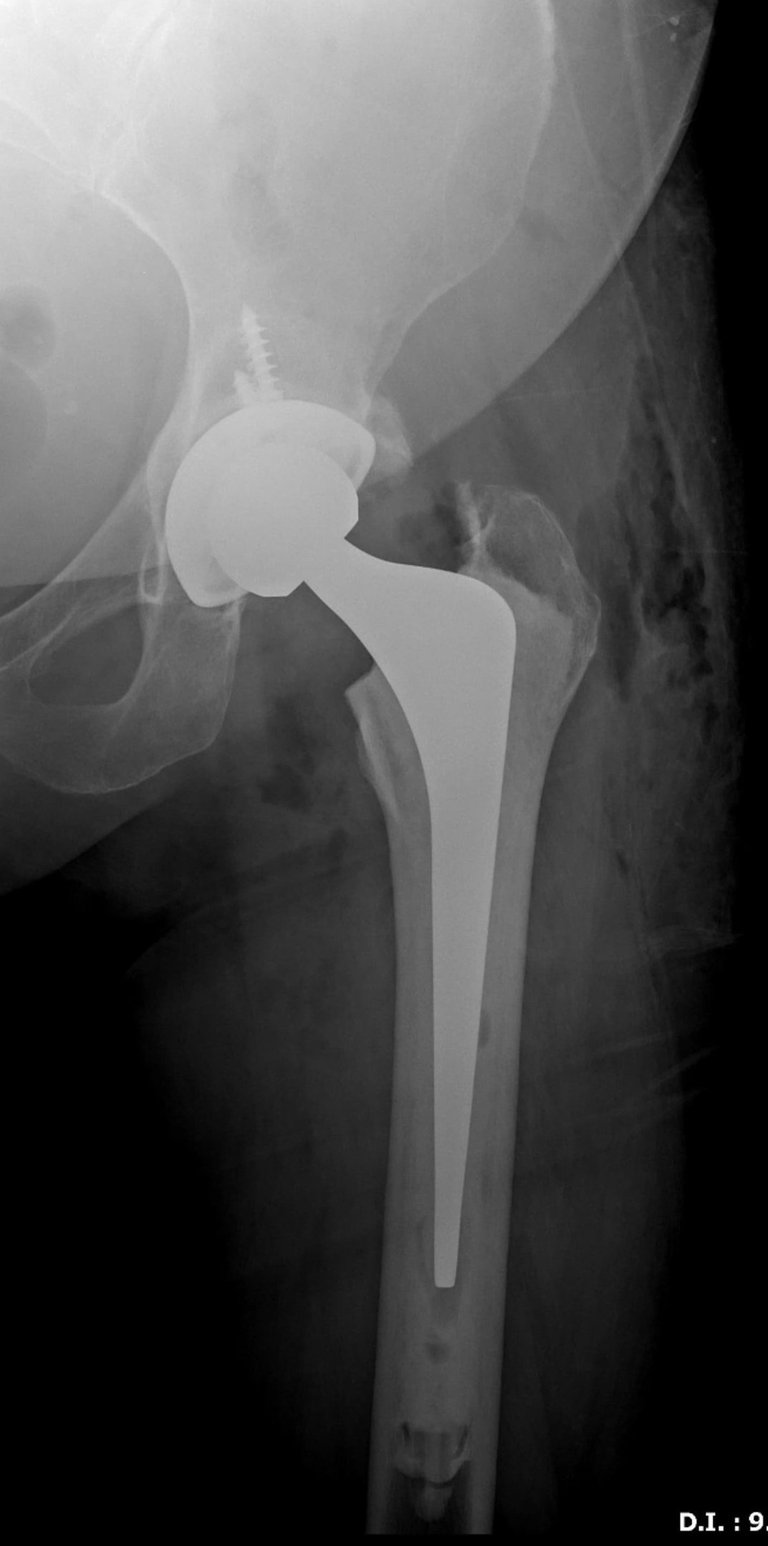

A artroplastia total do quadril é uma das cirurgias ortopédicas mais realizadas no mundo. Entre os diversos fatores que influenciam o sucesso da cirurgia, a forma de fixação dos componentes protésicos é um dos mais relevantes. Neste artigo, vamos explicar as principais diferenças entre prótese cimentada e não cimentada, abordando suas indicações, vantagens e limitações.

A prótese cimentada utiliza cimento ósseo (polimetilmetacrilato) para promover a fixação imediata dos componentes ao osso. Essa técnica é amplamente utilizada em pacientes idosos, com baixa densidade mineral óssea ou em casos de fratura do colo do fêmur.

Na prótese não cimentada, os componentes apresentam superfícies porosas ou revestidas com materiais como hidroxiapatita, que permitem a osteointegração. A fixação ocorre biologicamente, à medida que o osso cresce e se incorpora ao implante.

Estudos populacionais mostram que ambas as técnicas apresentam sobrevidas comparáveis quando bem indicadas. Em pacientes jovens e ativos, a fixação não cimentada tem mostrado bons resultados com menor taxa de afrouxamento. Em idosos com osso osteoporótico, a cimentação ainda é preferida por garantir estabilidade imediata. A prótese híbrida (copo cimentado e haste não cimentada) também tem sido uma alternativa com bons resultados em grupos selecionados.